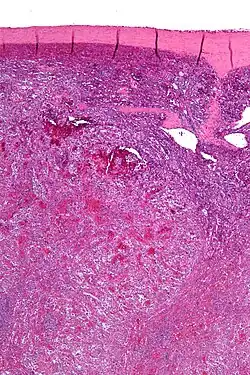

Low magnification micrograph of a littoral cell angioma. H&E stain.

Littoral cell angiomas show in CT scans. They are diagnosed by pathologists by taking a sample of the tumour via Fine Needle Aspiration or Core Needle Aspiration or from a splenectomy. Histologically, they have anastoming small vascular channels and cystic spaces with papillary projections.[2]